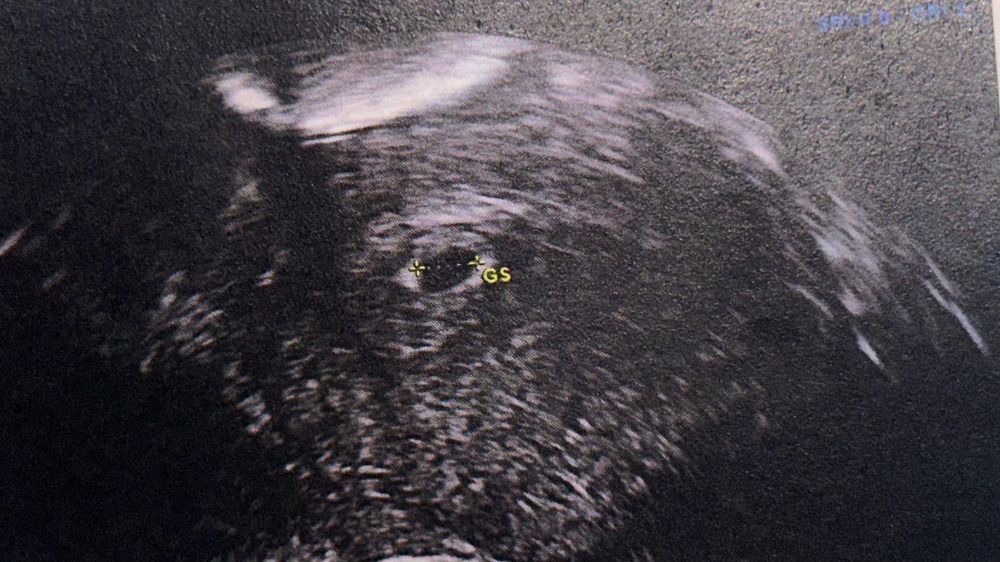

Нет. Это похоже на плодное яйцо, но очень маленькое.

Ксюня, желточный мешок внутри плодного яйца. Выглядит как колечко. У вас очень маленькое ПЯ, меньше, чем на 5 недель. Желточный мешочек появляется при больших размерах ПЯ

ЛанаРей, есть такое фото, приблизьте пожалуйста - мне кажется там виднеется колечко - что скажете? ) Изображение

Ксюня, честно, не вижу. Вы понимаете-фото скана узи это ни о чем. Нужно смотреть, крутить, выводить разные срезы. На одном срезе может не быть ничего, а на другом все- и желточный и эмбрион. Нужно смотреть описание узи. У вас размер плодного яйца 4 мм. Там в принципе еще не может быть никакого желточного

Судя по буквам GS это гестационный пузырь (мешок) это полость жидкости, которая окружает эмбрион. Пока эмбриончика у вас по узи не видно (срок скорее всего маленький)

Марьяна, 5 недель и 2 дня - так переживаю (((